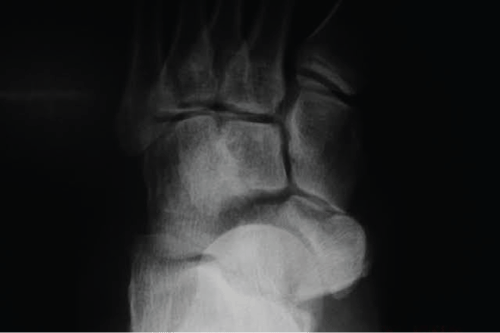

The patient underwent surgery on the same day, with open reduction and fixation with two Kirchner wires. The first one, crossed between the medial cuneiform, navicular and talus, and the other fixed between the navicular and cuboid (Figure 2).

Figure 2: Fixation with two crossed K-wires. One between the medial cuneiform, navicular and talus, and another between the navicular and cuboid.